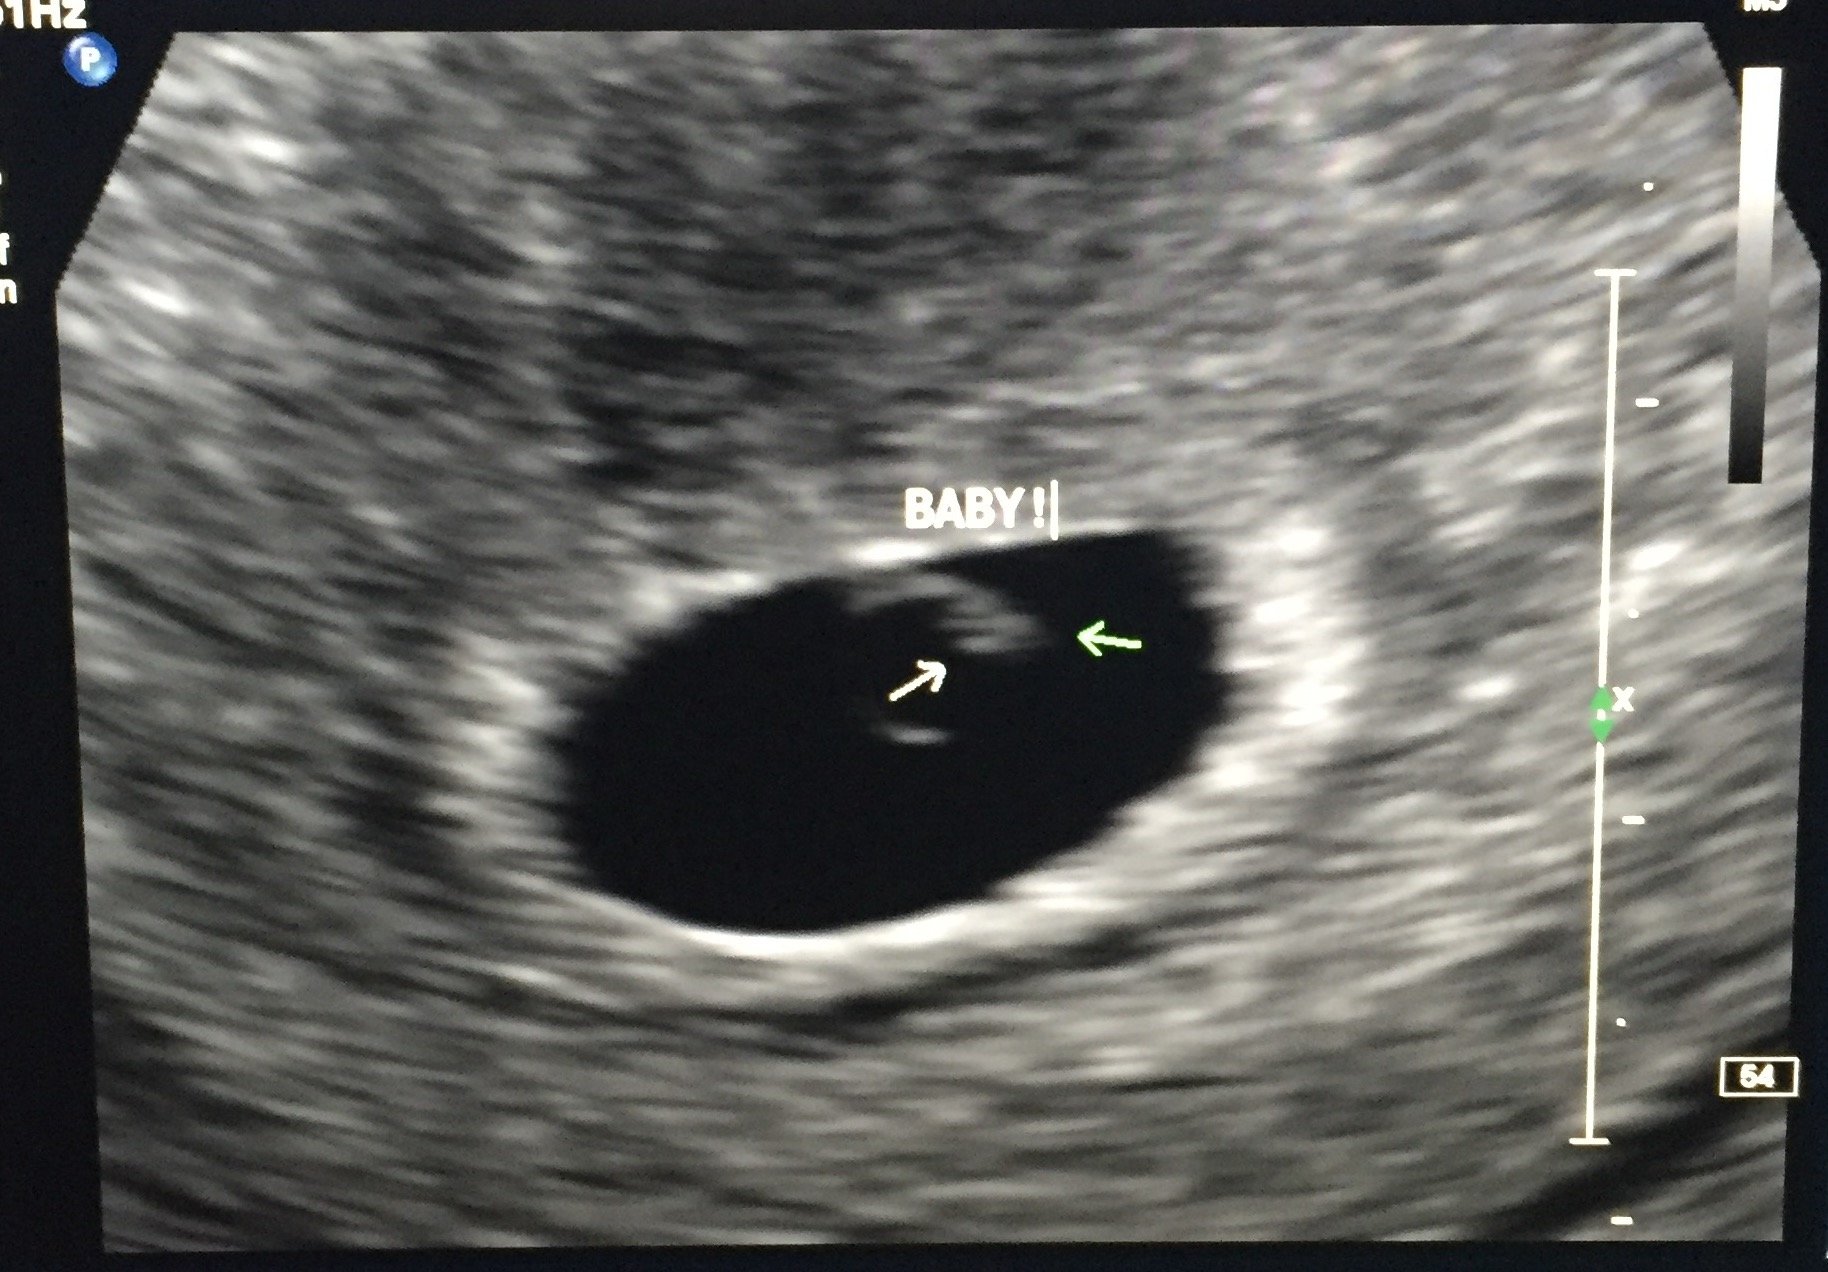

Had another check today at the RE. Left with a picture of a definite IUP with yolk sac & maybe more inside. Couldn't find heartbeat yet but the RE was happy with everything today. I go back next week.

It looks super tiny but you can definitely see stuff in the sac!

I didn't want to start an US thread (though I think we should have one) for fear of jinxing myself! But I will share with you ladies Sorry it is sideways!!